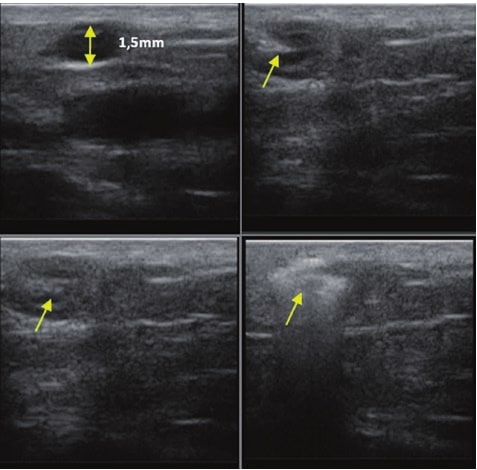

La sonographie Doppler permet l’imagerie des gros vaisseaux et des perforantes qui sont généralement situés dans les couches plus profondes du tissu sous-cutané (fig. 1). Malheureusement, la sonographie conventionnelle n’est pas capable d’imager les vaisseaux plus petits. Afin de visualiser les vaisseaux plus petits situés près de la surface de l’épiderme et dans la couche supérieure du tissu sous-cutané, l’EHF est utilisée (fig. 1). Grâce à l’utilisation de transducteurs dont les fréquences sont supérieures à 20 MHz, une image échographique à haute résolution est obtenue dans laquelle nous pouvons différencier des structures qui sont plus petites que 0,1 mm. Cependant, plus la résolution est élevée, moins la pénétration du faisceau ultrasonore dans les couches de la peau est profonde. Par conséquent, selon le transducteur et l’appareil, il est possible de pénétrer la peau jusqu’à une profondeur maximale de 20–30 mm. Une telle pénétration, associée à une haute résolution d’image, permet l’évaluation de vaisseaux sanguins même très petits (fig. 2). Pendant l’examen avec l’utilisation de transducteurs à haute fréquence, on peut évaluer avec précision le trajet et l’emplacement des petits vaisseaux dans la peau. Cela est particulièrement pertinent pour la sélection de la méthode de fermeture des vaisseaux et la planification de la procédure, car en pratique, la surface de la peau ne montre très souvent qu’un petit nombre de vaisseaux ou un léger fragment de vaisseau – ce n’est qu’après l’examen US que nous pouvons déterminer leur nombre réel et leur trajet. Pour une fermeture efficace du vaisseau, il est nécessaire de le faire sur toute sa longueur. Elle ne doit pas se limiter au fragment vu « à l’œil nu » à la surface de la peau, car la fermeture du fragment entraînera sa recanalisation rapide(7). Fréquemment, le vaisseau visible à la surface de la peau change de trajet, devient plus tortueux et se déplace vers les couches plus profondes de la peau(8). Par conséquent, le trajet de la veine et des perforantes doit être bien connu et déterminé avant la procédure. L’EHF permet également l’imagerie des perforantes entre les petits vaisseaux. De plus, outre l’évaluation du trajet et de l’anatomie, l’image échographique, grâce au logiciel d’échographie, permet également de déterminer les paramètres de base tels que le diamètre du vaisseau, l’épaisseur de sa paroi, la profondeur dans la peau ainsi que la présence ou l’absence de perfusion à l’intérieur du vaisseau(6) (fig. 3). Grâce au transducteur électronique multi-éléments d’une fréquence de 40 MHz introduit sur le marché par Ultrasonix, il est également possible de visualiser la perfusion des vaisseaux en mode Doppler couleur (fig. 4).